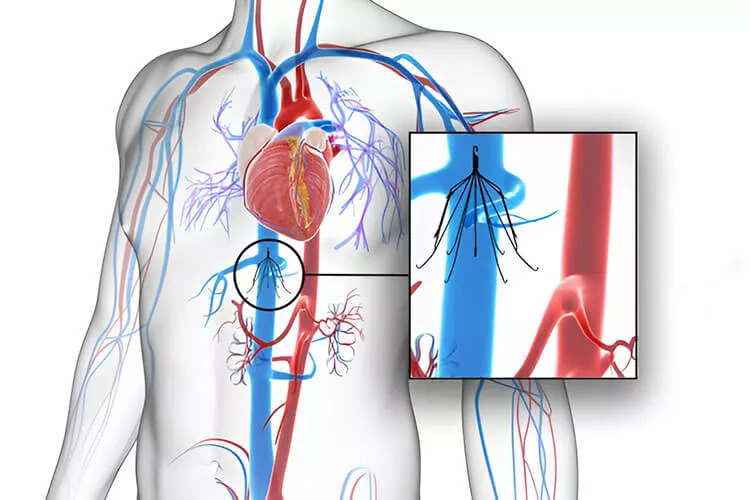

Kavální filtry (KF) se používají od roku 1972. Cílem jejich zavádění je zabránit plicní embolii (PE) a snížit tak morbiditu a mortalitu pacientů. Již první výsledky ale ukázaly pokles PE pouze o 50 % bez snížení mortality, navíc se 70% zvýšením rizika hluboké žilní trombózy (HŽT) v čase. Při antikoagulační léčbě je přitom riziko PE nízké. Implantace KF byly rozšířeny zejména v USA, ale ekonomická zátěž spojená s tímto postupem vede od roku 2010 k poklesu jejich využití, zejména permanentních KF. Dostupnost odstranitelných KF vedla k uvolnění indikací. Avšak ani u dočasných KF není jejich odstranění jisté. Pro medicínské zdůvodnění použití KF jsou jen omezené důkazy. Studií je málo, navíc roste výskyt komplikací. Kdy je tedy vhodné KF použít?

Indikační kritéria použití KF se v jednotlivých doporučeních liší. Česká angiologická společnost (ČAS) doporučuje použití KF u pacientů s tromboembolickou nemocí (TEN), u nichž je kontraindikována antikoagulace, vyskytnou-li se komplikace antikoagulační léčby vyžadující její přerušení, antikoagulace selže nebo dojde při antikoagulační léčbě k progresi hluboké žilní trombózy (HŽT). Existují ale i další relativní indikace KF u pacientů s TEN, jako je vlající trombus v dolní duté žíle (DDŽ), neschopnost udržet adekvátní hodnoty antikoagulační léčby masivní PE s reziduální HŽT, trombolýza u pacientů s ileofemorální HŽT, chronická TEN léčená trombendarterektomií, recidiva PE u pacienta s KF, non-compliance s antikoagulační léčbou, vysoké riziko komplikací antikoagulační léčby. Profylaktické indikace KF zahrnují trauma, velký chirurgický výkon či závažný zdravotní stav u pacientů s vysokým rizikem TEN. Zavedení KF má také své kontraindikace. Patří mezi ně atrézie DDŽ, trombóza či nádorový trombus v DDŽ, nemožnost cévního přístupu a průměr DDŽ > 40 mm. Relativními kontraindikacemi jsou sepse a alergie na kov KF.

Zavedení KF může být spojeno s krátkodobými i dlouhodobými komplikacemi, jako jsou patologie v místě punkce (4–11 %), zlomení KF (1–2 %), jeho migrace (0–18 %) či malpozice – nejčastěji angulace (1–9 %), perforace (0–41 %), penetrace, například do střevního lumen nebo do retroperitonea (8–19 %), vytvoření trombu v KF (2–30 %), ale i embolizace fragmentů KF (1 %). Mezi komplikace KF lze zařadit i selhání jeho odstranění. To může být způsobeno angulací KF, kdy jej nelze zachytit háčkem, dalším důvodem může být KF „zarostlý“ do stěny DDŽ, penetrace KF či nemožnost žilního přístupu. Dočasný KF je vždy třeba odstranit co nejdříve. KF lze vyjmout, pokud je jeho odstranění bezpečné a technicky možné. Vždy je nejprve třeba provést zobrazovací vyšetření. KF odstraňujeme, pokud má pacient nízké riziko recidivy TEN (i při eventuálním vysazení antikoagulace), toleruje antikoagulační léčbu, v KF není velká trombóza a očekávaná délka života je delší než 6 měsíců. Pokud odstranění provést nelze, je potřebná konverze na permanentní KF. Pacientům je také možné ponechat KF, pokud si to přejí. Pokud je v KF trombus, je jeho odstranění spojeno s rizikem PE, které stoupá s velikostí trombu. Otázkou zde je vždy účinnost antikoagulační léčby. V případě pochybností, týkajících se rizika závažné PE, je vhodné ponechat KF v DDŽ.